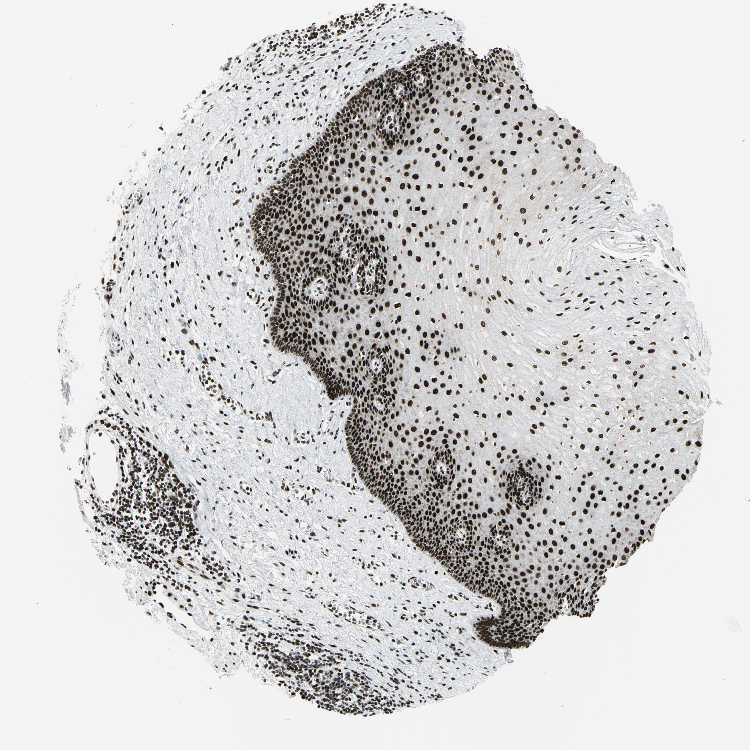

Antibody CAB004208

Squamous epithelial cells High